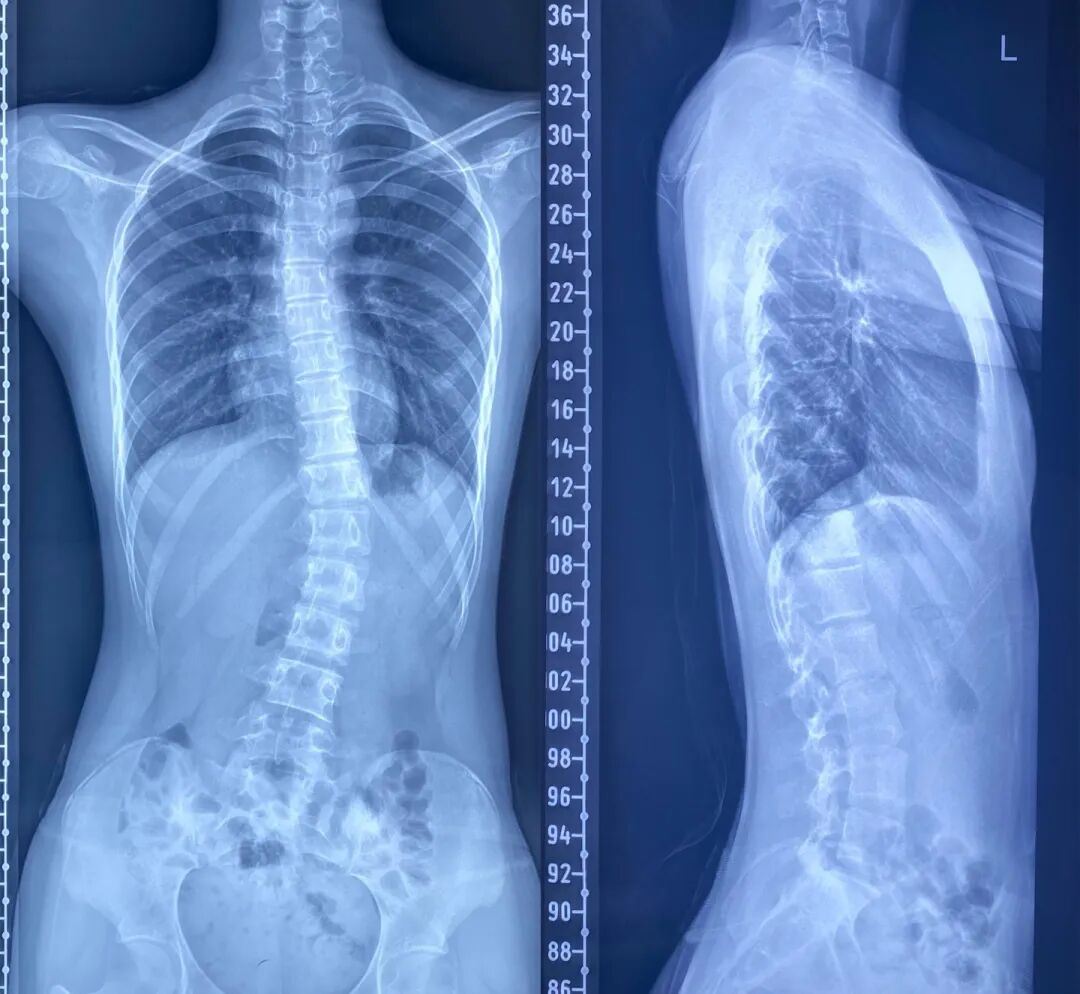

正常人的脊柱从背面看是一条直线,而我们常说的脊柱侧弯,就是站立在后面观察时,显示人体明显左右不对称,严重者会有疼痛、麻木及无力等症状。

正面

侧面

脊柱侧弯,是指脊柱一个或数个节段向侧方发生弯曲或伴有椎体旋转的脊柱三维畸形,包括冠状位、矢状位和轴位上的序列异常。常见的有先天性脊柱侧弯、特发性脊柱侧弯,以及神经肌肉性脊柱侧弯等。